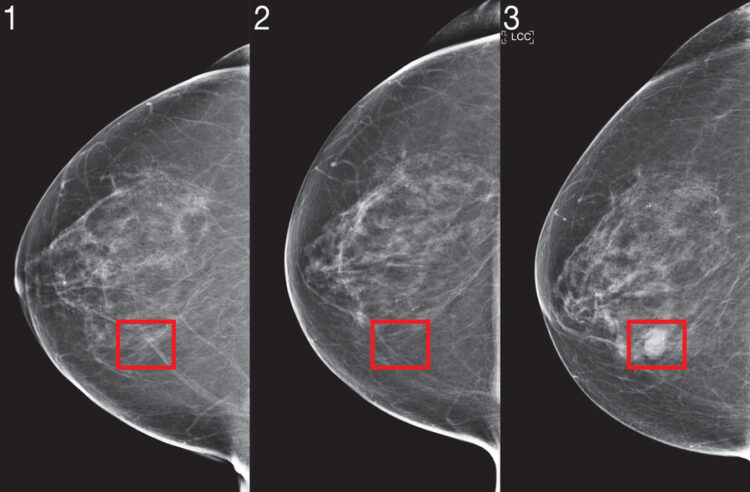

Për ta kapur kancerin më herët, duhet të parashikojmë se kush do e ketë atë në të ardhmen. Natyra komplekse e parashikimit të rrezikut është forcuar nga mjetet e inteligjencës artificiale (AI).

Dy vjet më parë, një ekip shkencëtarësh nga Laboratori i Shkencave Kompjuterike dhe Inteligjencës Artificiale të MIT (CSAIL) dhe Klinika Jameel demonstruan një sistem mësimi të thellë për të parashikuar rrezikun e kancerit duke përdorur vetëm mamografinë e një pacienti. Modeli tregoi premtime të rëndësishme dhe madje edhe përfshirje të përmirësuar: ishte po aq i saktë për gratë, gjë që është veçanërisht e rëndësishme duke pasur parasysh se gratë me ngjyrë kanë 43 për qind më shumë gjasa të vdesin nga kanceri i gjirit.

Por për të integruar modelet e rrezikut të bazuara në imazhe në kujdesin klinik dhe për t’i bërë ato gjerësisht të disponueshme, studiuesit thonë se modelet kishin nevojë për përmirësime algoritmike dhe vërtetim në shkallë të gjerë në disa spitale për të provuar qëndrueshmërinë e tyre.

Për këtë qëllim, ata përshtatën algoritmin e tyre të ri “Mirai” për të kapur kërkesat unike të modelimit të rrezikut. Mirai modelon së bashku rrezikun e një pacienti në disa pika kohore në të ardhmen dhe mund të përfitojë opsionalisht nga faktorët klinik të rrezikut si mosha ose historia familjare, nëse ato janë të disponueshme. Algoritmi është projektuar gjithashtu për të prodhuar parashikime që janë të qëndrueshme për variancat e vogla në mjediset klinike, si zgjedhja e makinës së mamografisë.

Ekipi e trajnoi Mirai-n në të njëjtin grup të dhënash prej mbi 200,000 provimesh nga Spitali i Përgjithshëm i Massachusetts (MGH) nga puna e tyre e mëparshme dhe e vërtetoi atë në grupe testesh nga MGH, Instituti Karolinska në Suedi dhe Spitali Memorial Chang Gung në Tajvan. Mirai tani është instaluar në MGH dhe bashkëpunëtorët e ekipit po punojnë në mënyrë aktive në integrimin e modelit në kujdes.

Mirai ishte dukshëm më i saktë se metodat e mëparshme në parashikimin e rrezikut të kancerit dhe identifikimin e grupeve me rrezik të lartë në të tre grupet e të dhënave. Kur krahasuan grupet me rrezik të lartë në grupin e testeve MGH, ekipi zbuloi se modeli i tyre identifikoi gati dy herë më shumë diagnoza të kancerit në të ardhmen krahasuar me standardin aktual klinik, modelin Tyrer-Cuzick.

Mirai ishte po aq i saktë te pacientët e racave të ndryshme, grupmoshave dhe kategorive të densitetit të gjirit në grupin e testit MGH dhe në nëntipe të ndryshme të kancerit në grupin e testeve Karolinska.